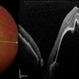

- multicolor

Heidelberg Spectralis - Description

- Multi-color fundus of a 30 yo female with PAMM OD.